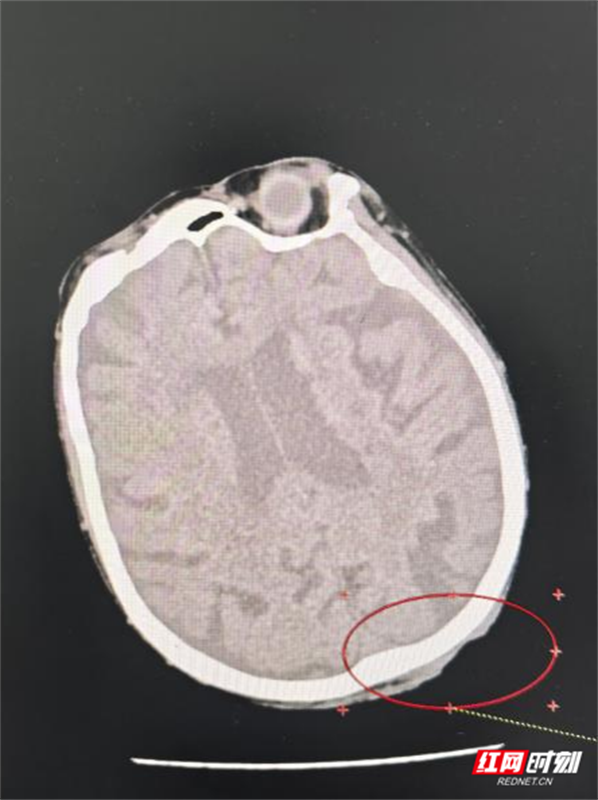

医生为谭奶奶进行了头部MRI等详细检查后,确诊她患“头皮恶性肿瘤鳞癌Ⅲ期”。这一结果让她和家人的心情跌落谷底——在他们看来,肿瘤本身就是难以治愈的疾病,更何况高龄老人还伴有多种基础疾病。